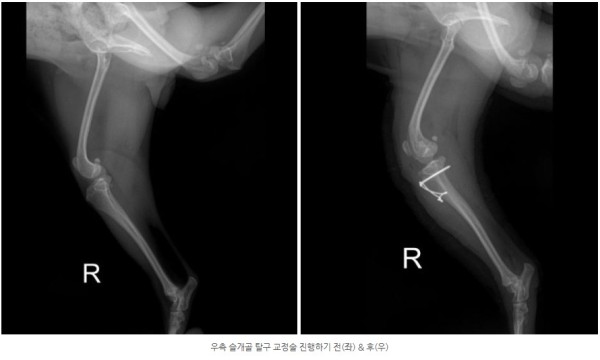

양쪽 모두 안쪽으로 슬개골이 빠지는 내측탈구 4기 상태가 확인되었고

통증의 근본 원인을 해결하기 위해 양측 모두 슬개골 탈구 교정술(MPL)을 진행하기로 결정하였습니다.

교정술 후 5일간 입원하여 24시간 케어를 받고 양호한 컨디션으로 퇴원한 아이는